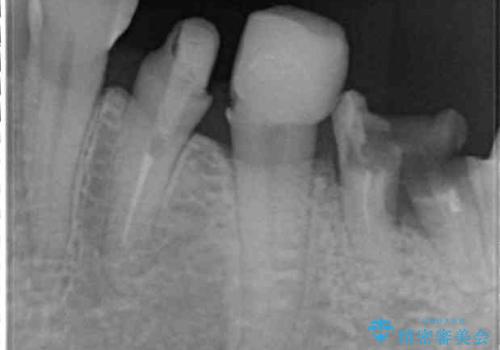

- 虫歯や歯の欠損を放置していることを気にして来院された患者様です。

下顎には抜歯が必要な歯があったため、抜歯後に治癒を待ち、上顎とともにオールセラミックブリッジにて補綴治療を行うこととしました。